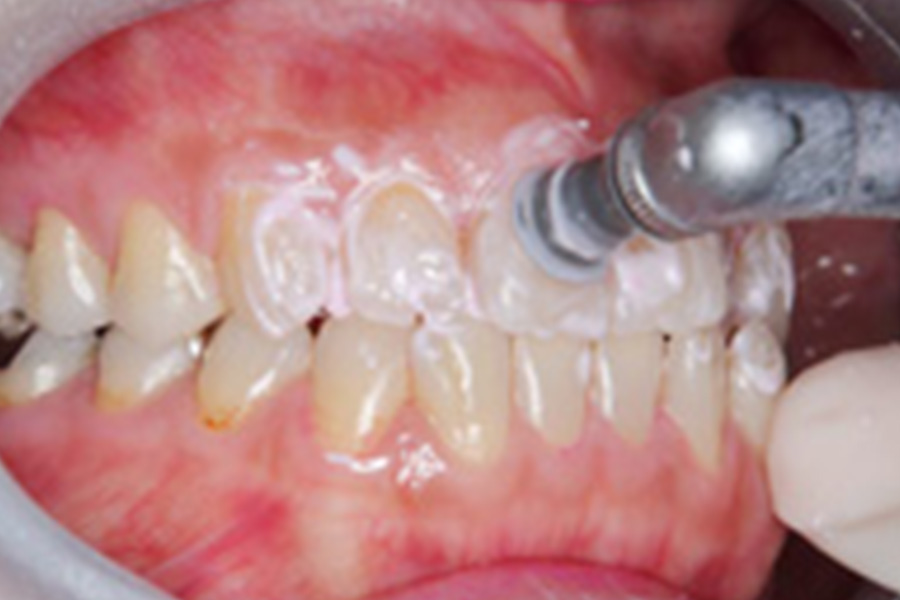

PMTC

PMTCはProfessional(専門家が) Mechanical(専用の機械で) Tooth(歯面を) Cleaning(クリーニングする)の頭文字をとっています。毎日隅々まで磨いている歯にも、取り切れていないバイ菌・バイオフィルム・歯垢・たばこのヤニなどが付着しています。これらの頑固な汚れを専用の機械で徹底的に落としていくのが「PMTC」です。

PMTCでは、治療のような痛みを感じることはございません。歯の表面がつるつるになり、とてもお口の中がさっぱりします。正しいセルフケアにプラスして、定期的に是非受診してください。